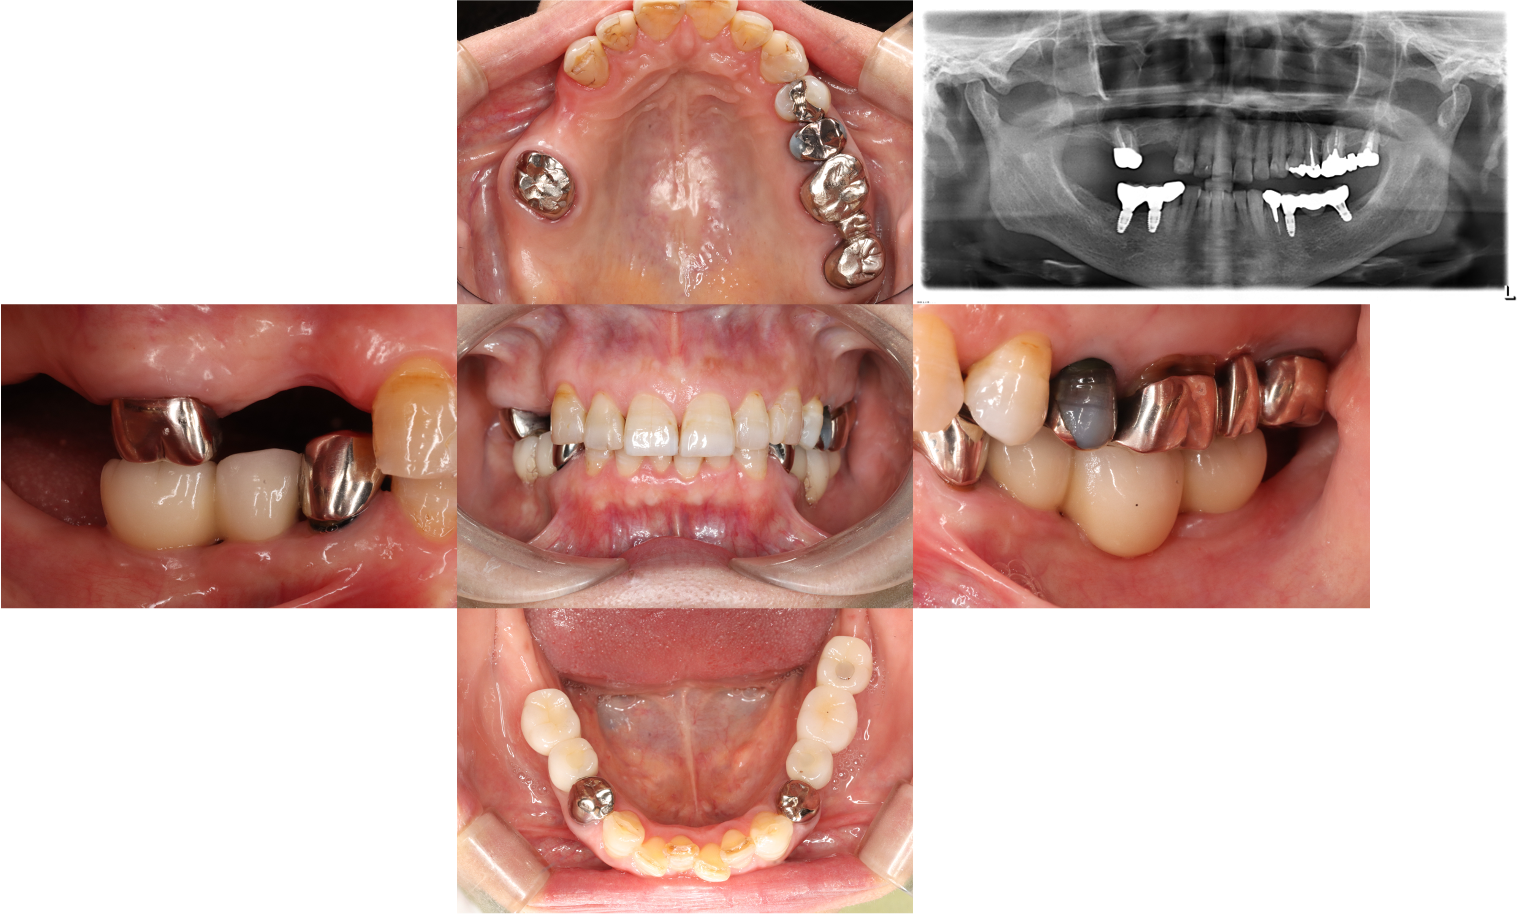

症例1

Before

.png)

After

患者さんの年齢/性別 | 女性/50歳代 |

主訴 | 奥歯でしっかりと食事が噛めない |

治療内容 | 左の奥歯は数年前に抜歯してから入れ歯を使用していて、右のブリッジとなっている奥歯で主に食事を噛んでいたとのこと。 |

治療期間/治療回数 | 5ヶ月/7回 |

費用 | CT 16,500円(税込) |

リスク・副作用 | 歯周病に感染・発症し重度に進行するとインプラントが抜けてしまうことがあります。また、手術後は数日間腫れが出る場合があります。 |